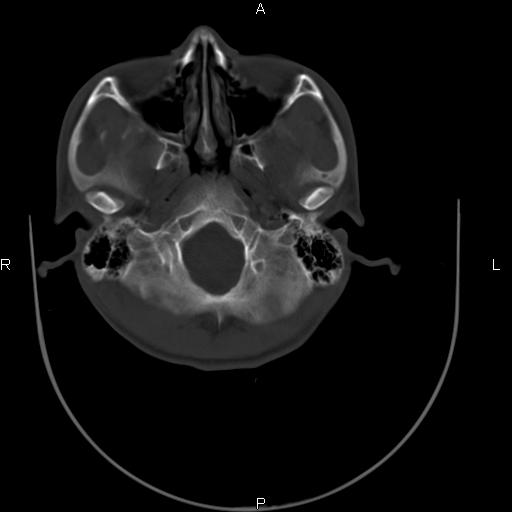

标题: CT27115:大家看一看,这孩子的颅骨表现?

两名中学生打架,脑质内未见异常,未上传。

感觉第2个颅缝密度高,额顶部板障有点厚,正常变异?地中海贫血?